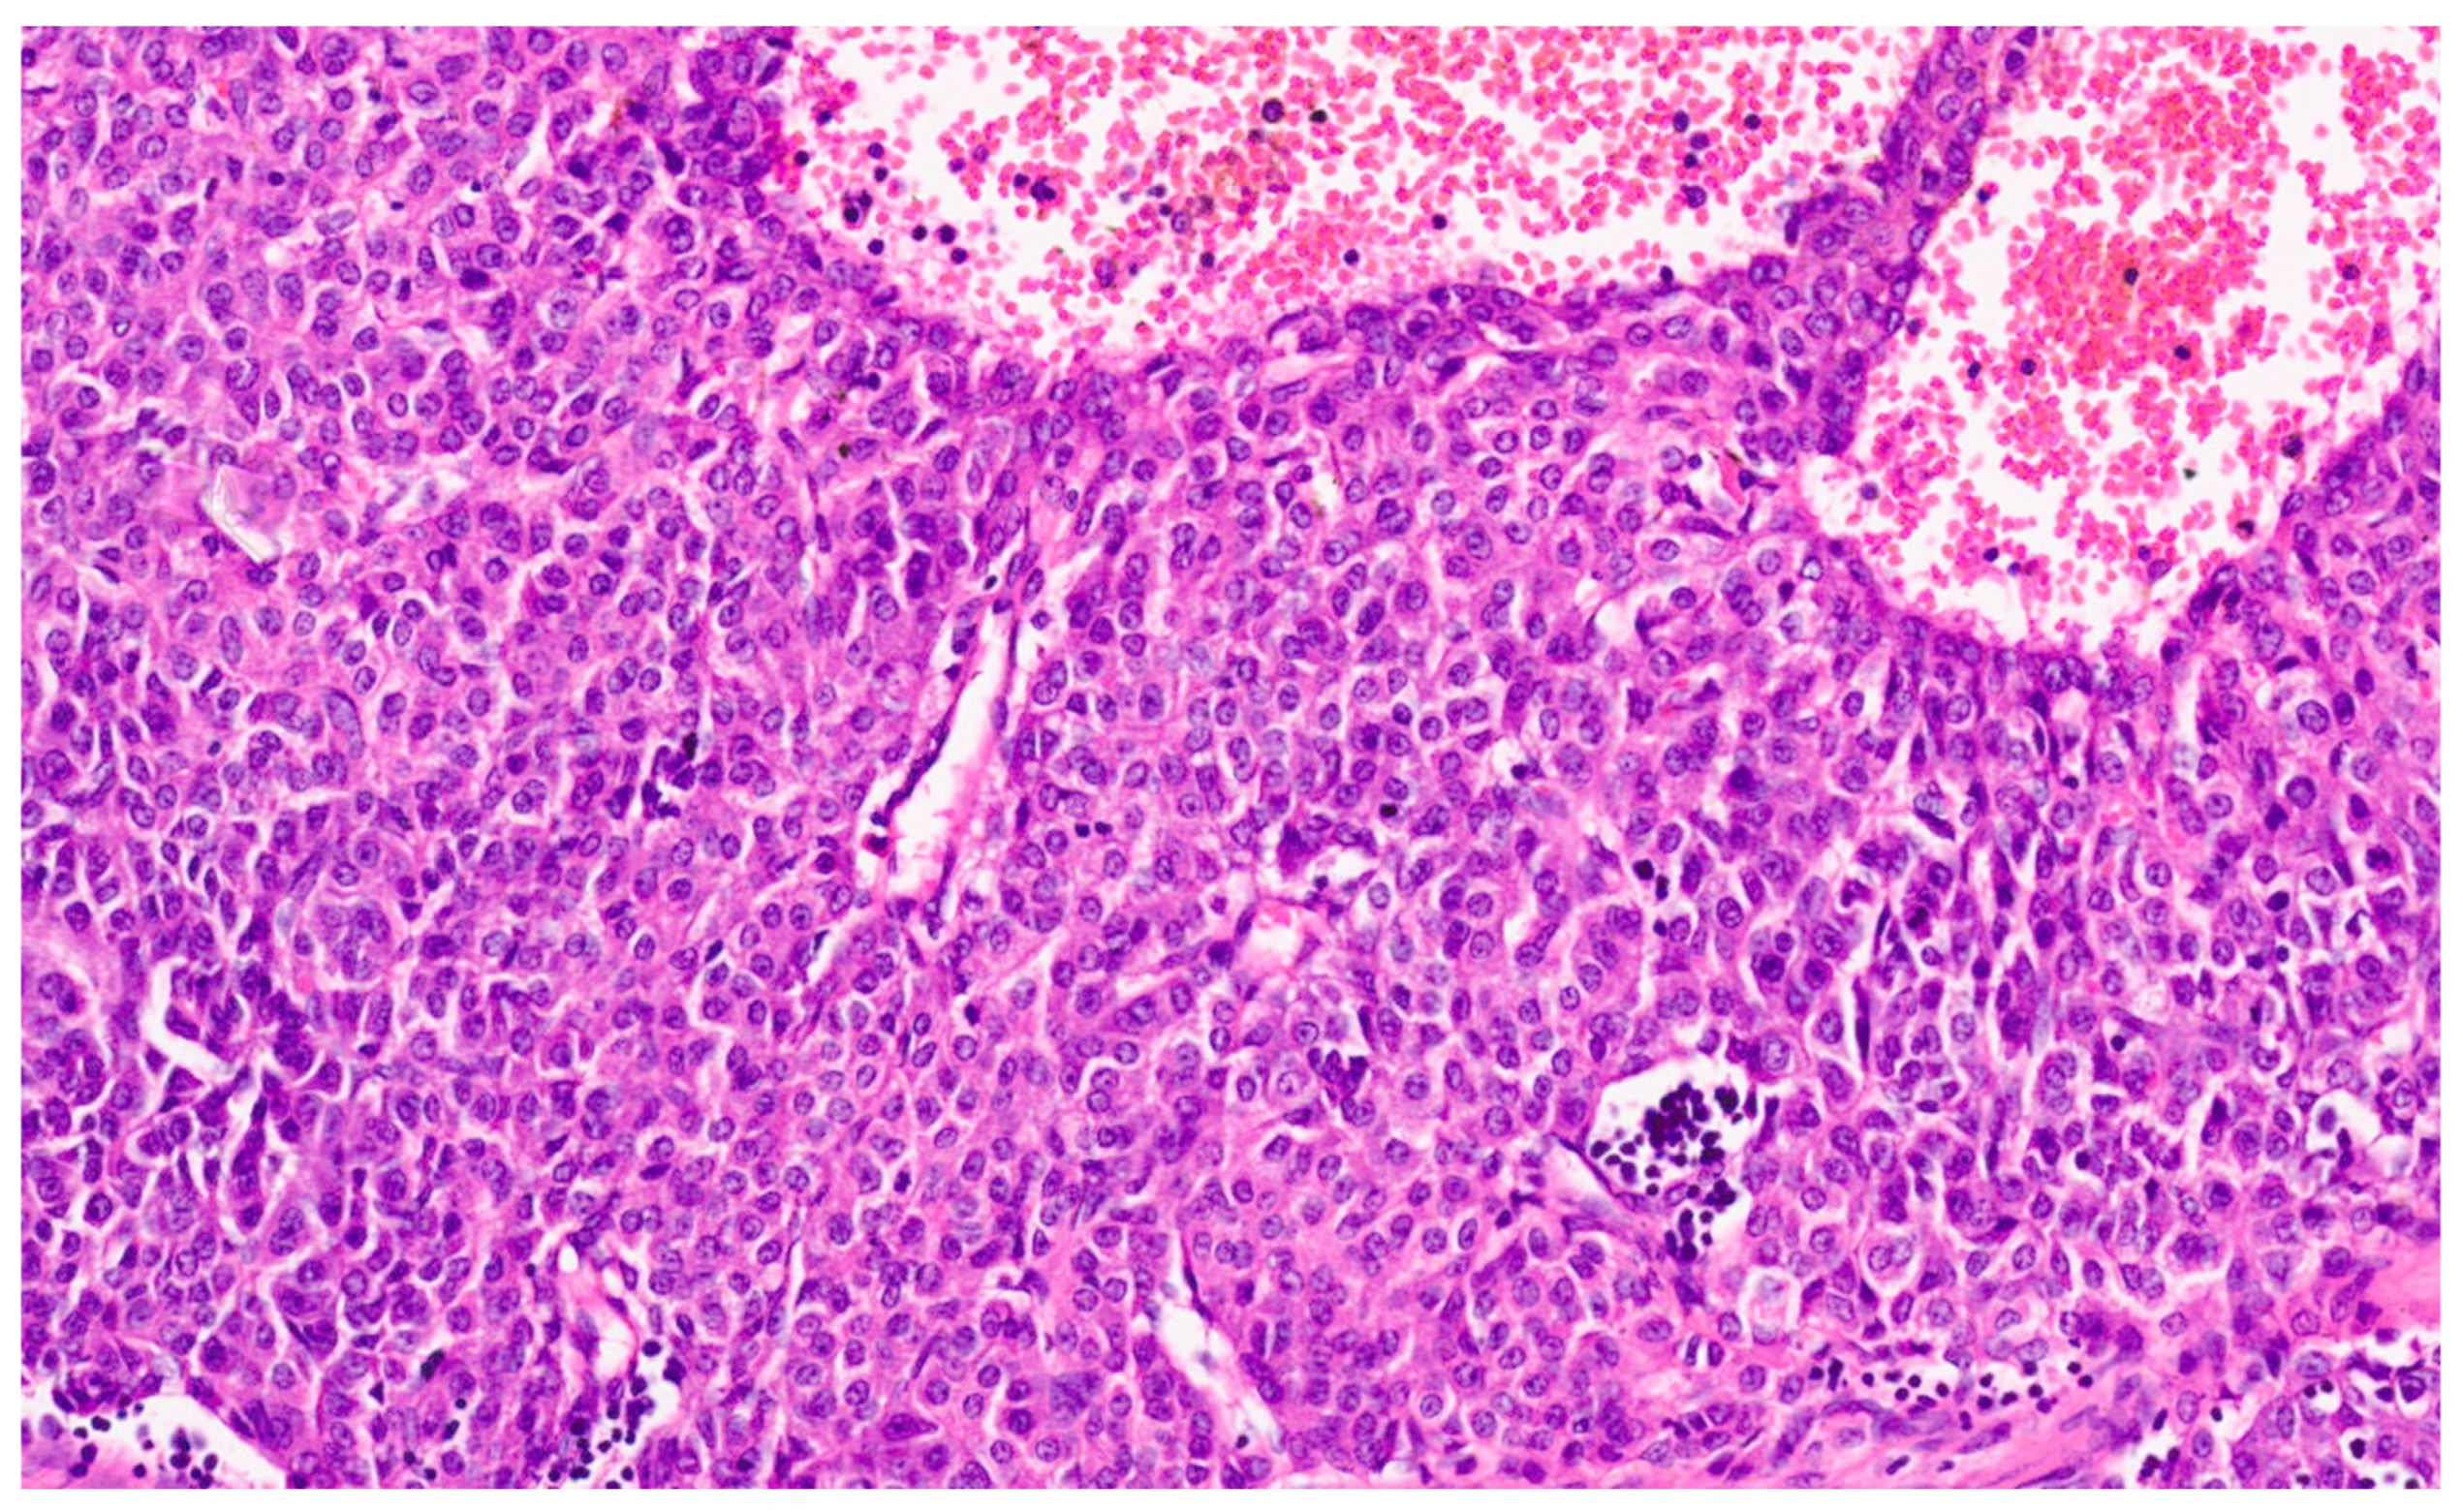

16.3. Pathology

| Histopathology | Well Differentiated | Moderately Differentiated | Poorly Differentiated |

|---|---|---|---|

| Arrangement | Trabeculae that are at least 3 cells thick and lined by sinusoids, pseudoacinar arrangement | Trabeculae that are 15–20 cells thick lined by sinusoids, pseudoacinar arrangement | Sheets or nests of cells not resembling hepatocytes. |

| Cells and nuclei | Resemble hepatocytes with mild nuclear pleomorphism, centrally placed round nuclei, and abundant cytoplasm | Moderate nuclear pleomorphism, large nuclei with prominent nucleoli and intranuclear inclusions, abundant cytoplasm. | High N/C ratio, nuclear pleomorphism, prominent nucleoli and intranuclear inclusions, numerous mitosis |

| Necrosis | Usually absent | May be seen | Present |

| Immunohistochemistry | Variable glypican 3 and glutamine synthetase levels. Negative for β-catenin nuclear staining | Glypican 3 and glutamine synthetase are positive in 50% of cases, β-catenin is variable | Glypican 3 and glutamine synthetase |